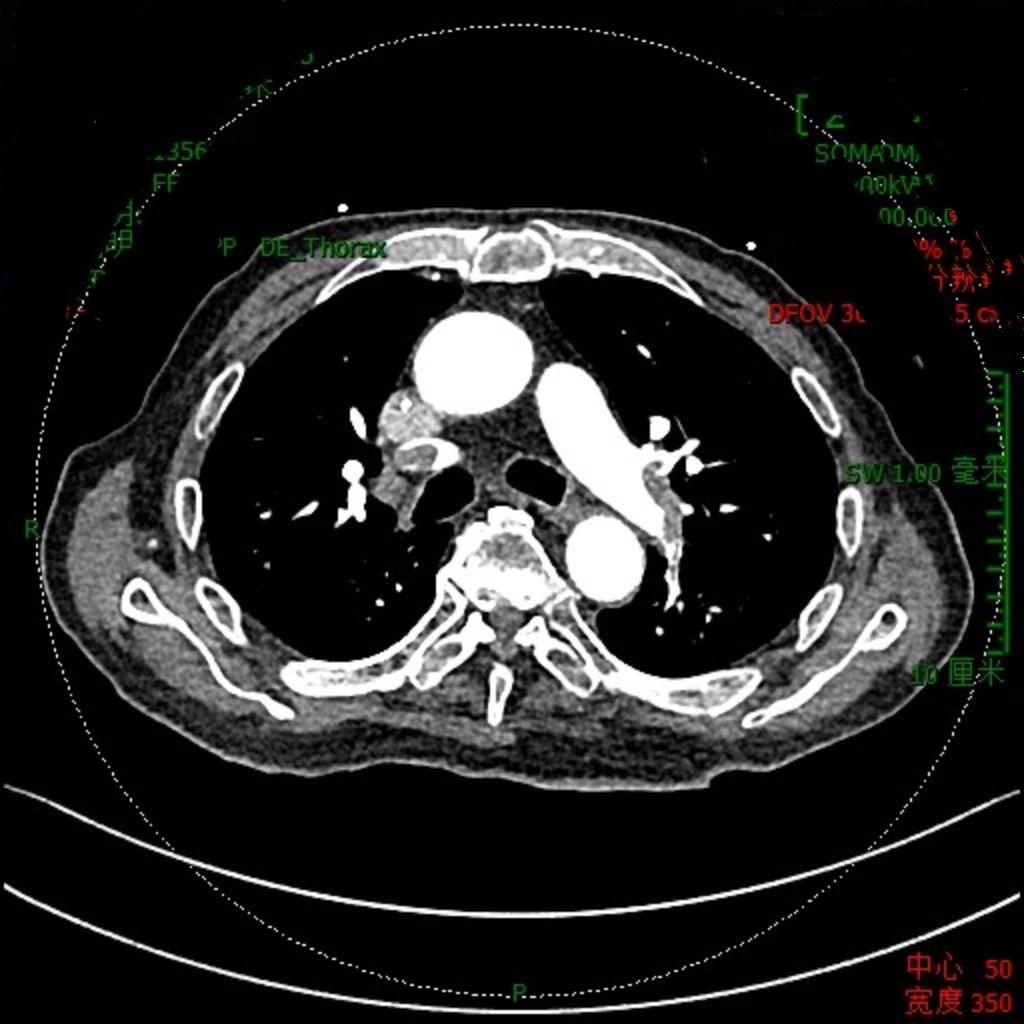

肺栓塞是血液肿瘤治疗中必须警惕的